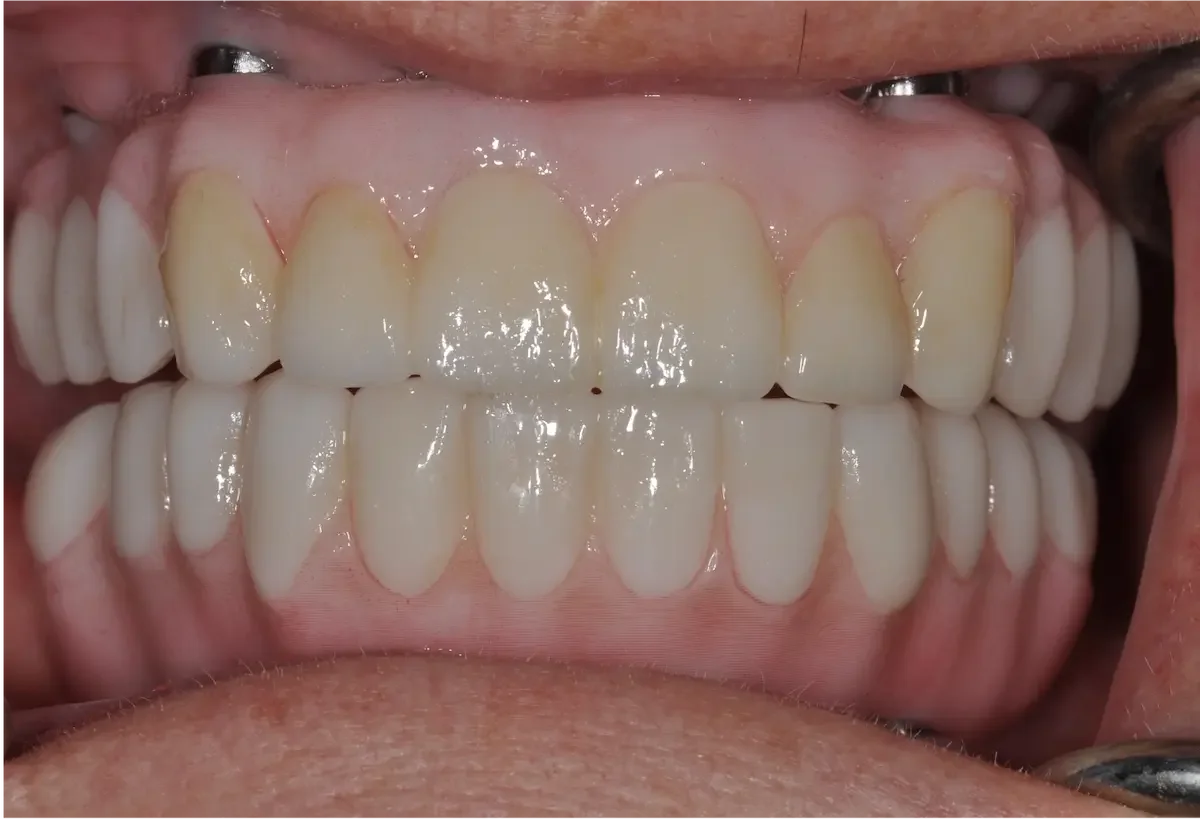

How We Restored a Front Tooth with a Dental Implant — Start to Finish

They’re what people notice first. So when a front tooth is missing or damaged — whether from trauma, decay, or failed restorations — it’s not just about replacing it. It’s about doing it perfectly in the smile.

In this case study, we’ll walk you through one of the more complicated — and rewarding — procedures we do at our practice: a front tooth dental implant. You’ll see how much thought, planning, and precision goes into restoring one small tooth… and why every step in the dental implant process matters.

Over the next few weeks or months, we monitor soft tissue healing. Sometimes we adjust the temporary to guide gum shaping. Patience here pays off — rushing this stage can lead to esthetic failure. One of the biggest risks in front teeth implants is gum recession!Final Crown

Once everything is stable, we place the final custom crown. Shade, translucency, shape, and surface texture are all matched to your natural teeth so the implant blends in seamlessly.

If all the steps are followed carefully — especially tissue shaping and crown customization — it will be nearly impossible to tell it’s not your original tooth. Check out our video case study to see more.

Final Thoughts

Replacing a front tooth with an implant isn’t just dental work — it’s dental artistry. Cosmetic dentistry is more than just placing an implant in your jawbone. And when it’s done right, the result is a smile that looks and feels completely natural.